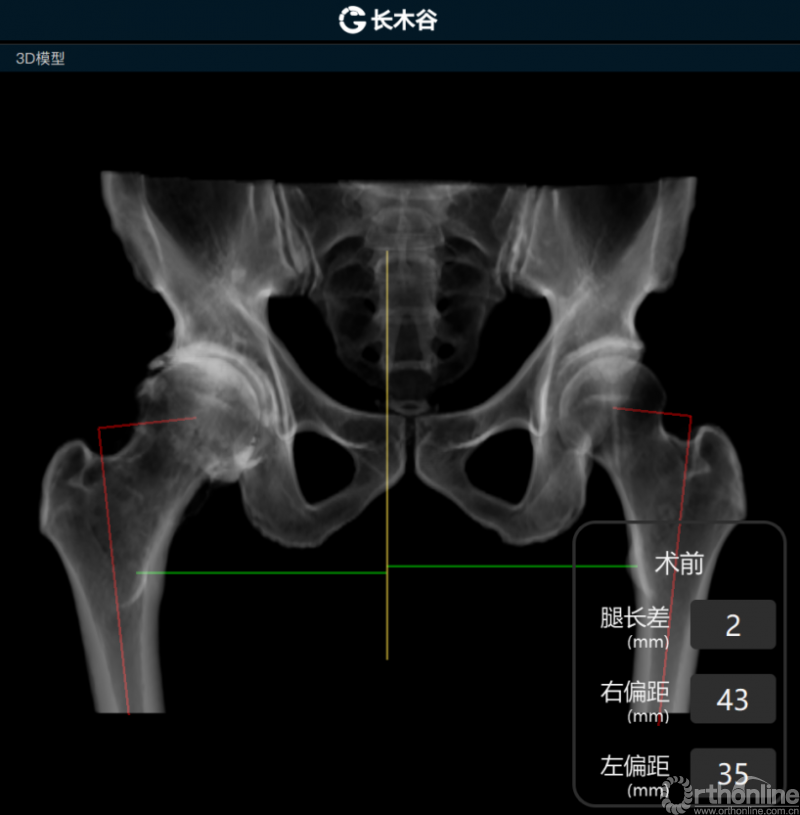

AI HIP系统对患者术前偏距与腿长差进行智能测量与评估

而后,由人工智能判断患者双侧腿长差及股骨偏心距大小,如图可见,由于长期受到的髋关节撞击征影响,该患者术前腿长差为2mm,右侧股骨偏心距为43mm,明显大于左侧股骨偏心距35mm。